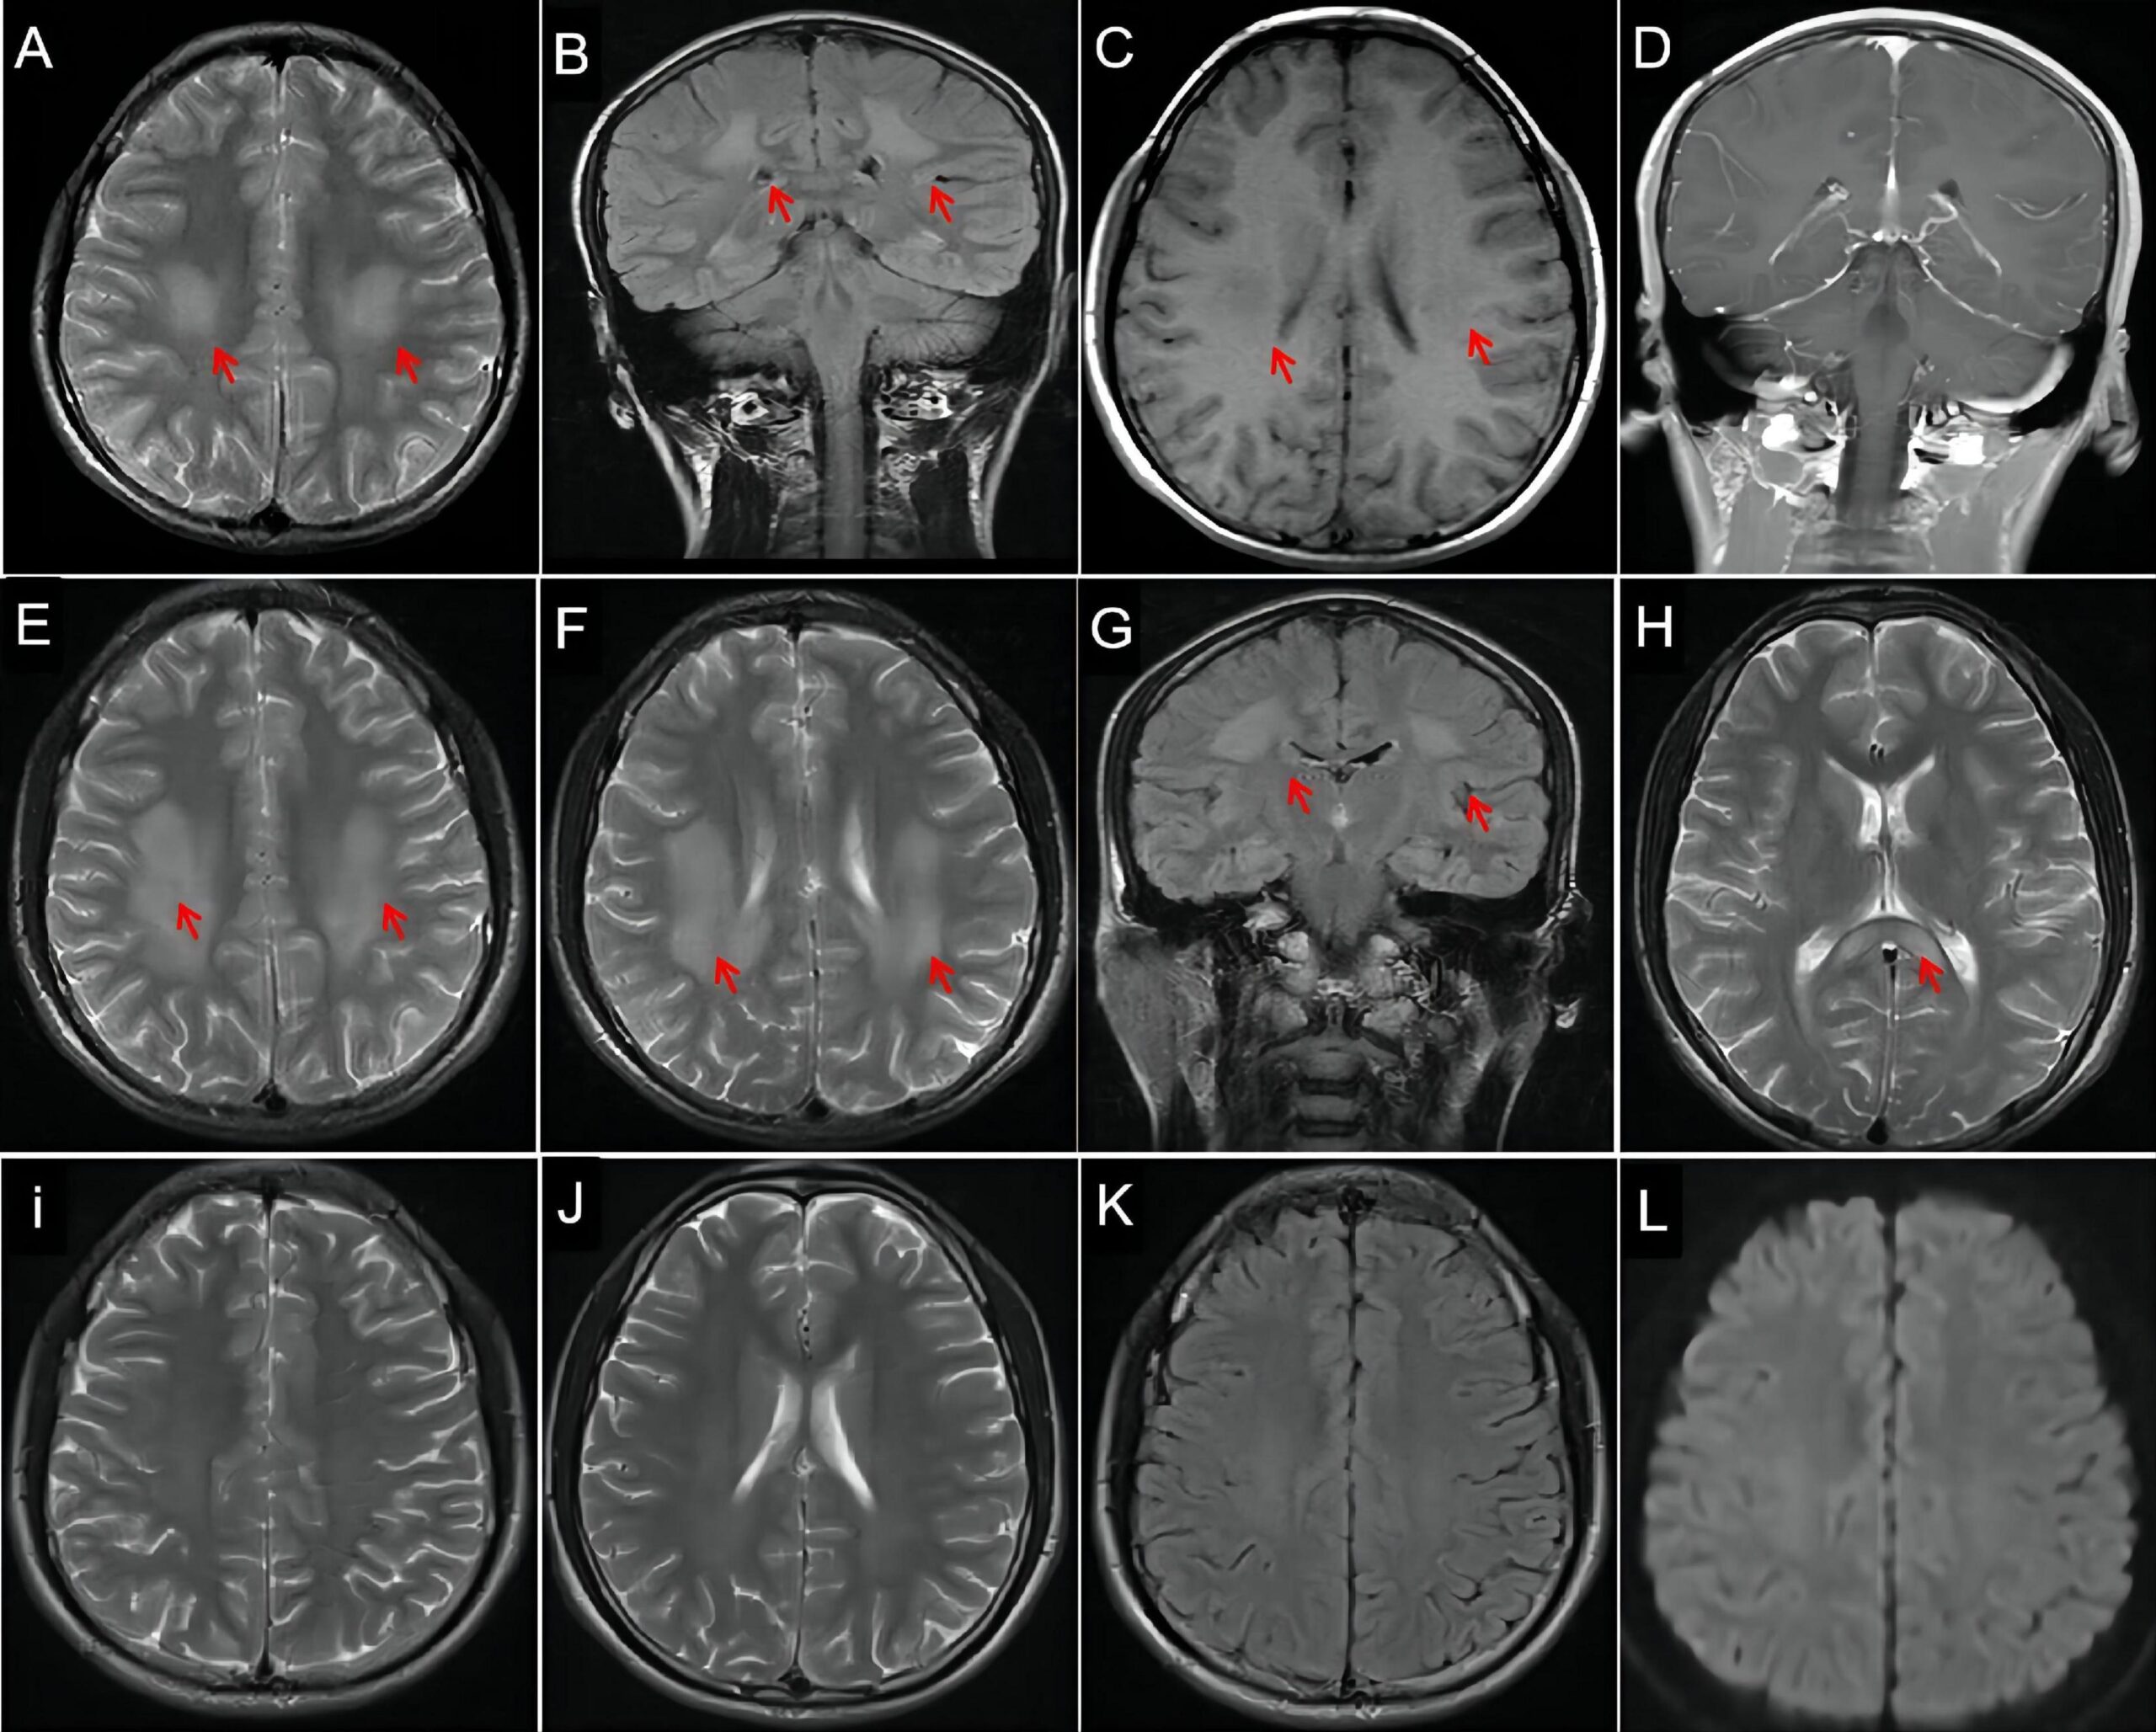

画像診断

- MRI:

- 神経や筋肉の詳細な画像を提供し、神経の損傷や筋肉の萎縮を視覚的に確認するために使用されます。特に診断が困難な場合に補助的に用いられます 。

画像引用元:frontiers

以下に、CMTのMRI画像上の典型的な特徴について詳しく説明します。

末梢神経の特徴

- 神経肥大 (Nerve Hypertrophy):

- CMT1Aなどのタイプでは、末梢神経の肥大がMRIでしばしば観察されます。これは、ミエリン鞘の異常形成や肥厚によるもので、特に脛骨神経や坐骨神経など大きな神経で顕著です。

- 神経の信号変化:

- 神経組織の信号強度の変化が見られ、これは神経の変性や脱髄によるものです。T2強調画像では、高信号を示すことがあり、神経の異常を示唆します (MIT App Inventor) 。

筋肉の特徴

- 筋萎縮 (Muscle Atrophy):

- CMT患者では、特に下肢の筋肉の萎縮が顕著に見られます。MRIでは、筋肉が薄くなり、筋肉量が減少していることが明らかになります。これにより、筋力低下や運動能力の低下が引き起こされます (Khan Academy) 。

- 脂肪の浸潤 (Fatty Infiltration):

- 筋肉が萎縮する一方で、脂肪組織が筋肉内に浸潤することがあります。T1強調画像では、筋肉が低信号を示し、脂肪が高信号を示すため、筋肉と脂肪のコントラストが明確になります (Scrabble Word Finder) 。